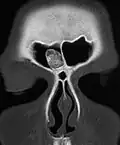

Остеома лобной пазухи на компьютерном томографе